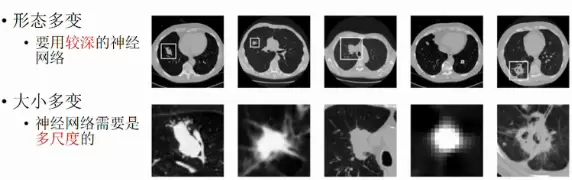

基于肺癌辅助诊断方面,在2017年的数据国际大赛上,本实验室学生团队和清华大学计算机系胡晓林副教授、张钹院士合作,获得了世界第一成绩,比赛内容为从CT图像预测肺癌的发病率。肺结节的形态多变且大小不一,需要运用比较复杂的深度神经网络和基于概率的贝叶斯网络协同来识别。我们利用了LUNA和DB3两个数据集上进行交替训练,总体达到了AUC=87%的结果,大致对应于80%的敏感率,和80%的特异性,医生水平大约为78%的敏感率,和80%的特异性。

肺结节示例